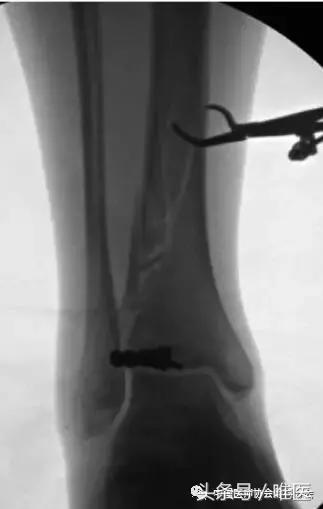

首先复位胫骨骨折的关节外部分,在髓内钉放置之前,胫骨远端关节面骨折进行稳定固定达到解剖复位,确保在髓内钉放置时不会出现关节内骨折移位。胫骨近端骨折部分的复位有助于关节表面的复位,例如与胫骨下关节面骨折邻接的螺旋形骨折中,当骨折较小或未移位时,可以进行经皮内固定。(图3)

图3:患者B的术中透视图像显示了在关节表面复位和固定时,进行胫骨骨折的经皮复位。